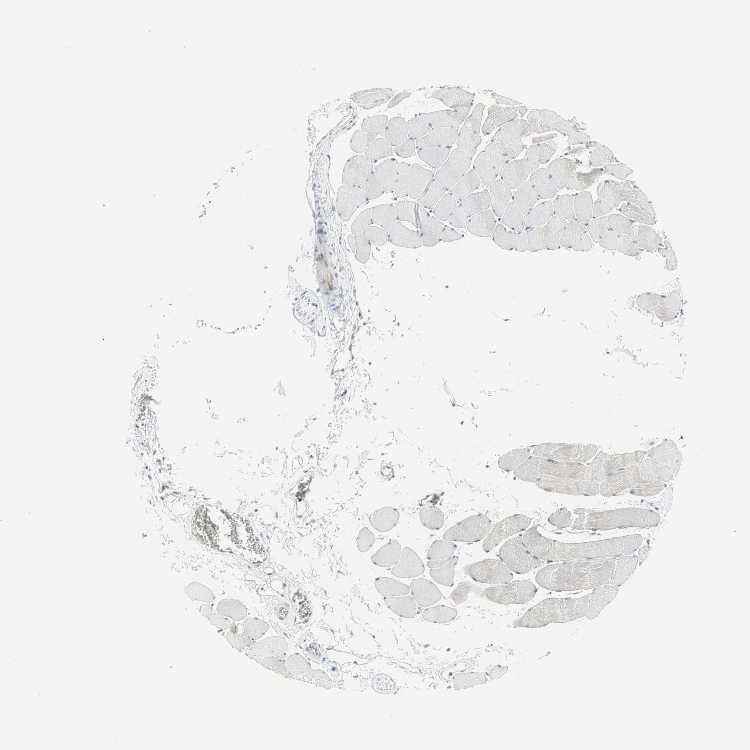

SKELETAL MUSCLE - Antibody stainingi

Antibody staining in the annotated cell types in the current human tissue is reported as not detected, low, medium, or high, based on conventional immunohistochemistry profiling in selected tissues. This score is based on the combination of the staining intensity and fraction of stained cells.

Each image is clickable and will lead to virtual microscopy that enables deeper exploration of all samples and also displays staining intensity scores, fraction scores and subcellular localization as well as patient and tissue information for each sample.

Antibody HPA005695Antibody CAB022068Antibody CAB035999Antibody CAB080052Antibody CAB080054Antibody CAB080098

Myocytes Not detectedHighNot detectedMediumNot detectedNot detected